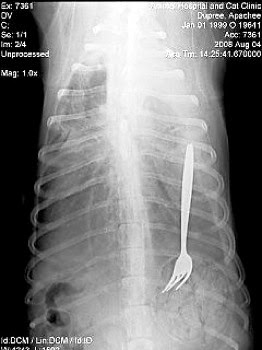

Să zicem că la animale e mai de înţeles, dar totuşi… cum să înghită un câine o furculiţă întreagă? Probabil era un câine de talie mare… că altfel…